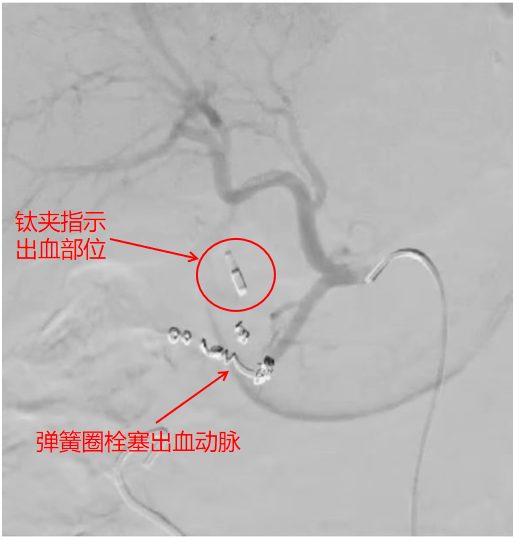

术中栓塞出血动脉的影像

手术室就位后,患者因为失血性休克出现了四肢湿冷、烦躁不安、呼吸紊乱等情况。麻醉科主治医师王晓宇迅速建立中心静脉通路,为患者输血、补液,维持循环稳定,曹战江与医师李子澎上台,行股动脉穿刺,结合增强CT以及消化内科医师内镜下留置的钛夹定位下,很快定位出血动脉为胃十二指肠动脉的一条分支。

由于出血动脉仅有2毫米,为顺利使导丝通过病变,李子澎通过栓塞出血点远端与近端的“三明治”栓塞技术精准栓塞动脉。术中动态监测显示,患者血红蛋白稳定并呈上升趋势,止血成功。患者安全返回病房后,医护团队继续守在床旁监测生命体征,动态复查血常规。凌晨6点,最新一次检验结果显示血红蛋白为6.8g/L,达到了正常值,所有人都长舒一口气:“终于平安了!”目前,患者已顺利康复出院。